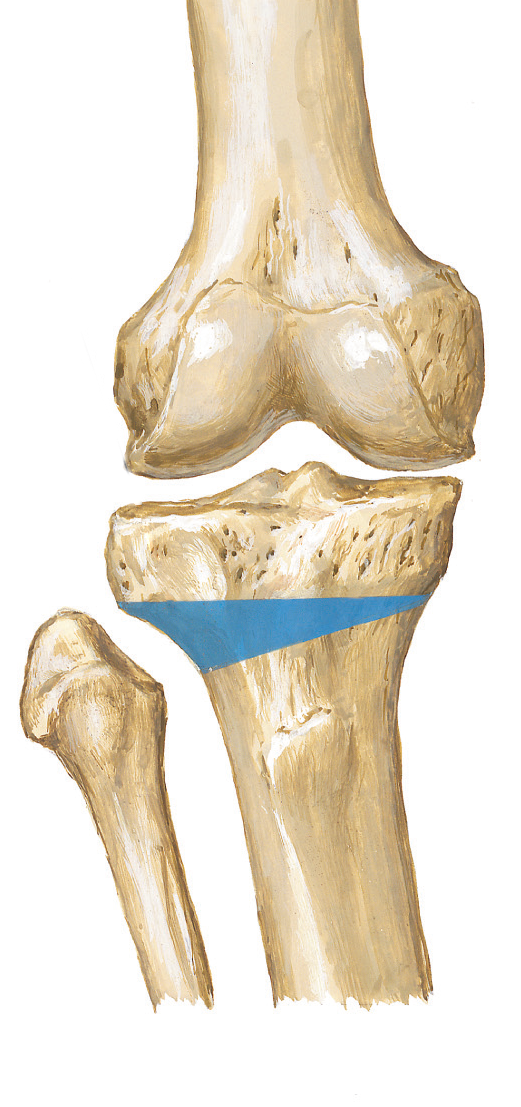

Bu ameliyat sırasında tibianın ya iç ya da dış tarafında kemik kesilir. İç taraftaki kesi arasına üçgen şeklinde kemik kama yerleştirilir ve plak ve vidalarla tespit edilir. Tibianın dış tarafındaki kesiden ise uygun ebatta bir kemik kama çıkarılır.

Böylece iç taraftaki kemik kesisi konulan kama ile açıldığında veya dış taraftaki kemik kesisi çıkarılan kama ile kapatıldığında bacak düzelir. Bu, dizin sağlıklı tarafındaki eklem aralığını daraltır ve hasarlı, artritli taraftaki eklem aralığını açar. Sonuç olarak diz ağırlığı daha eşit bir şekilde taşıyabilir ve ağrılı taraftaki baskıyı hafifletebilir.

B. Yüksek tibial osteotomi kesisi

C. Kemik kama çıkarılması ve dizilimin düzeltilmesi